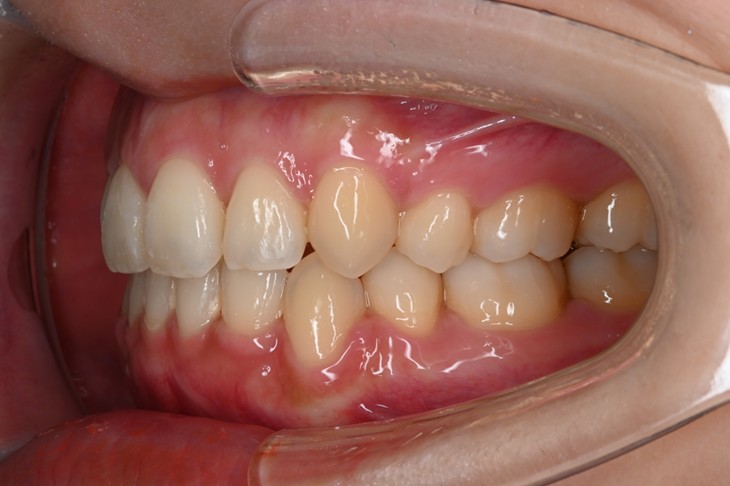

症例2:八重歯が気になる

| 患者様データ | 20代 女性 |

| 来院主訴 | 八重歯が気になる。 |

| 治療内容 | 八重歯を治すために上の親知らずを抜歯し、インビザラインにてマウスピース矯正を開始しました。かみ合わせを整えるためにゴムかけを行いました。 |

| 概算治療費 | 約85万円 |

| 治療期間 | 1年3ヶ月 |

| 通院回数 | 8回 |